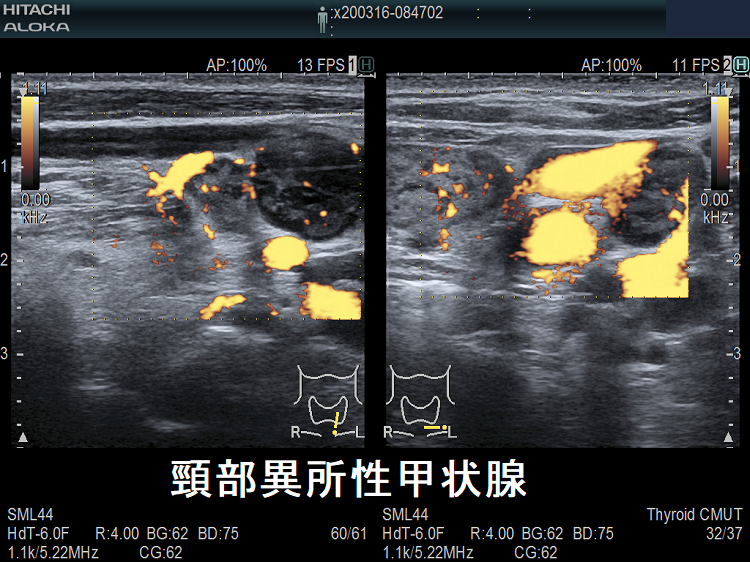

頚部異所性甲状腺

頚部異所性甲状腺(非腫瘍)

頸部および卵巣内の異所性甲状腺は全体の9.9%です(日臨28: 1784-1789, 1970.)。甲状腺と同エコー輝度の腫瘤が、甲状腺と連続性・非連続性に存在します。I-123 シンチグラフィーで異所性部位に取り込み(集積)を認めます。

橋本病の異所性甲状腺 超音波(エコー)画像 ドプラーモード

橋本病を合併した頚部異所性甲状腺:下極の副甲状腺と同じ位置にある異所性甲状腺。特徴的な2連構造で、甲状腺本体と同様の破壊性変化を認めます。